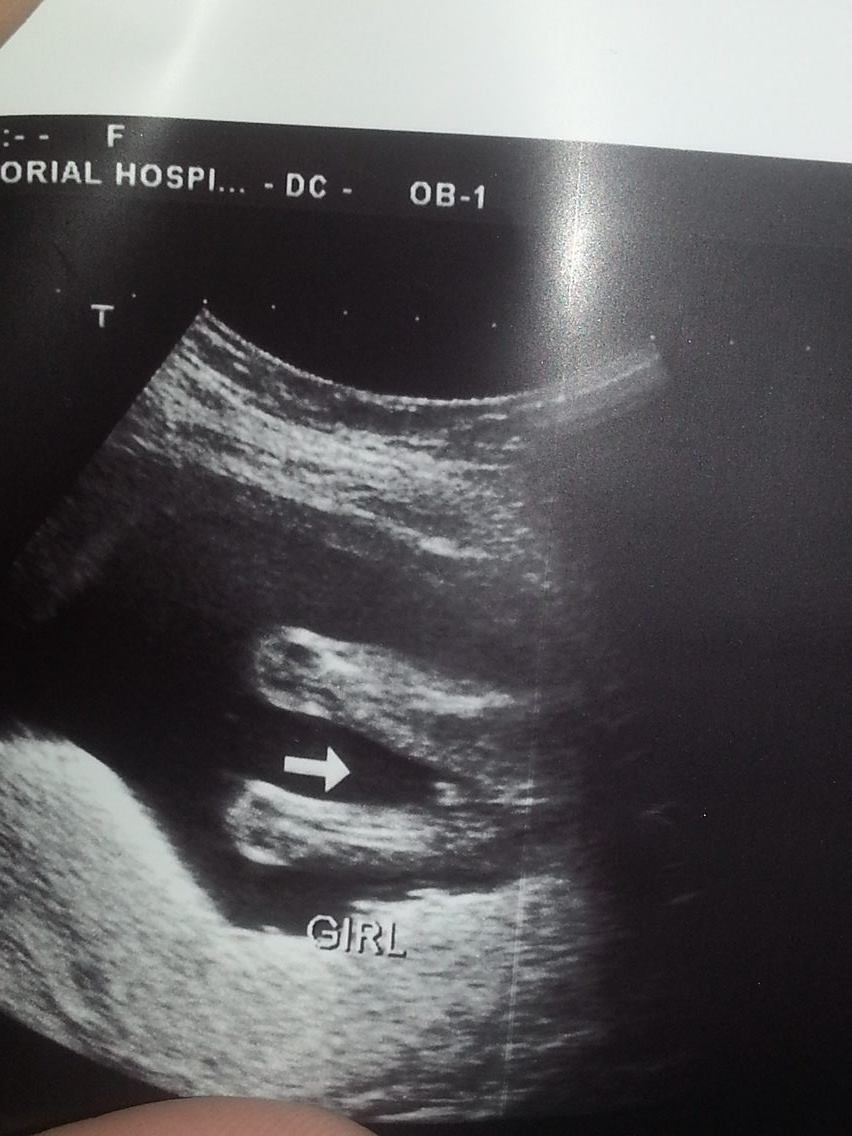

HELPPPP... Have been told: BOY (14wks), BOY (16wks), GIRL(17wks), & GIRL (18wks)

HELPPPP... Have been told: BOY (14wks), BOY (16wks), GIRL(17wks), & GIRL (18wks)!!

Absolutely completely confused & upset. A tech friend who works at our local hospital (so not an OB tech that views gender everyday, but does has experience & has been doing them for years) has been performing ultrasounds for me just out of excitement herself. I've so appreciated being able to watch my baby grow as I am high risk, & it keeps my mind at ease! BUT gender predictions have been a nightmare thus far. My latest just doesnt seem like normal "girl parts" to me. It is protruding far more than what I have seen on my two previous girls. The base of the the "three lines" isnt even attached at the bottom of the baby. Its odd to say the least. But some opinions will be greatly appreciated. My actual OB will be doing a gender u/s next week at 21 weeks so hopefully we will get some clarity. Regardless I feel like I will have a hard time trusting it & getting to bond with my SON or DAUGHTER :( ... hellllpAttachment 31823